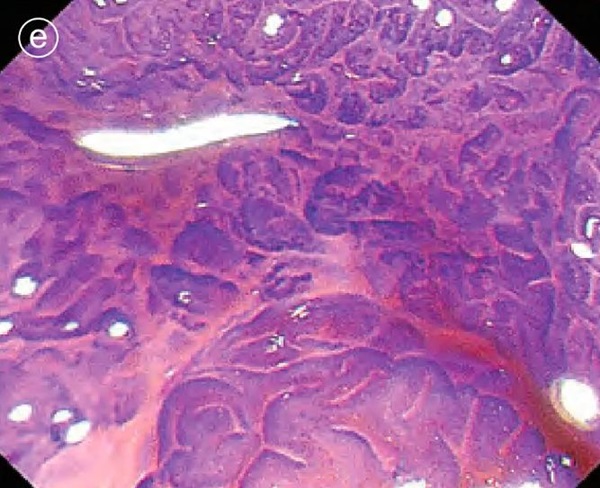

e. Enlarged image of crystal violet staining

in the center of the lesion was VI, slightly irregular, and no obvious submucosal infiltration was found .